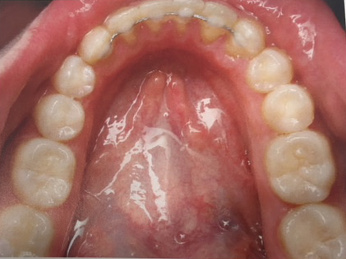

Fixed  Retainer

These consist of a thin stainless steel wire, which is permanently bonded behind the front teeth. We usually fit your fixed retainers when your braces are removed.